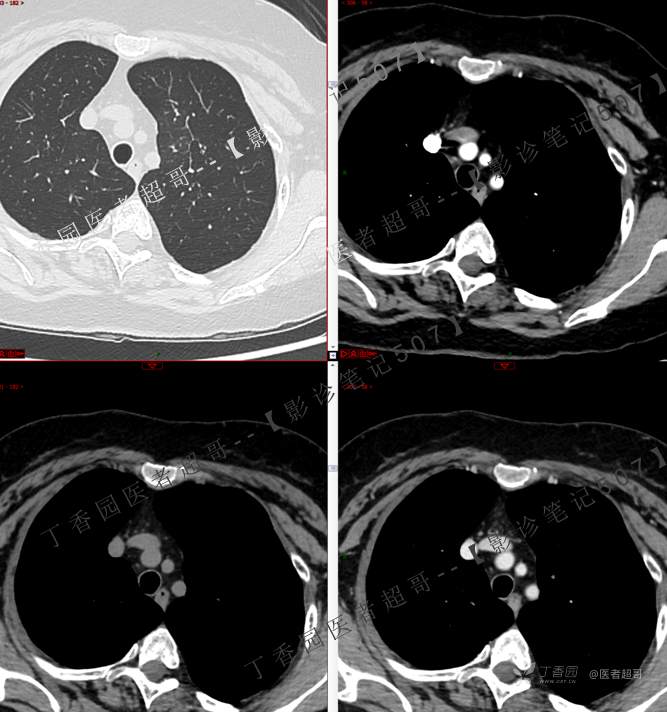

患者性别:女

患者年龄:50岁

简要病史:患者4月余前出现无明显诱因及病因出现胸痛,无咳嗽咳痰等表现。

小细胞肺癌 (54)